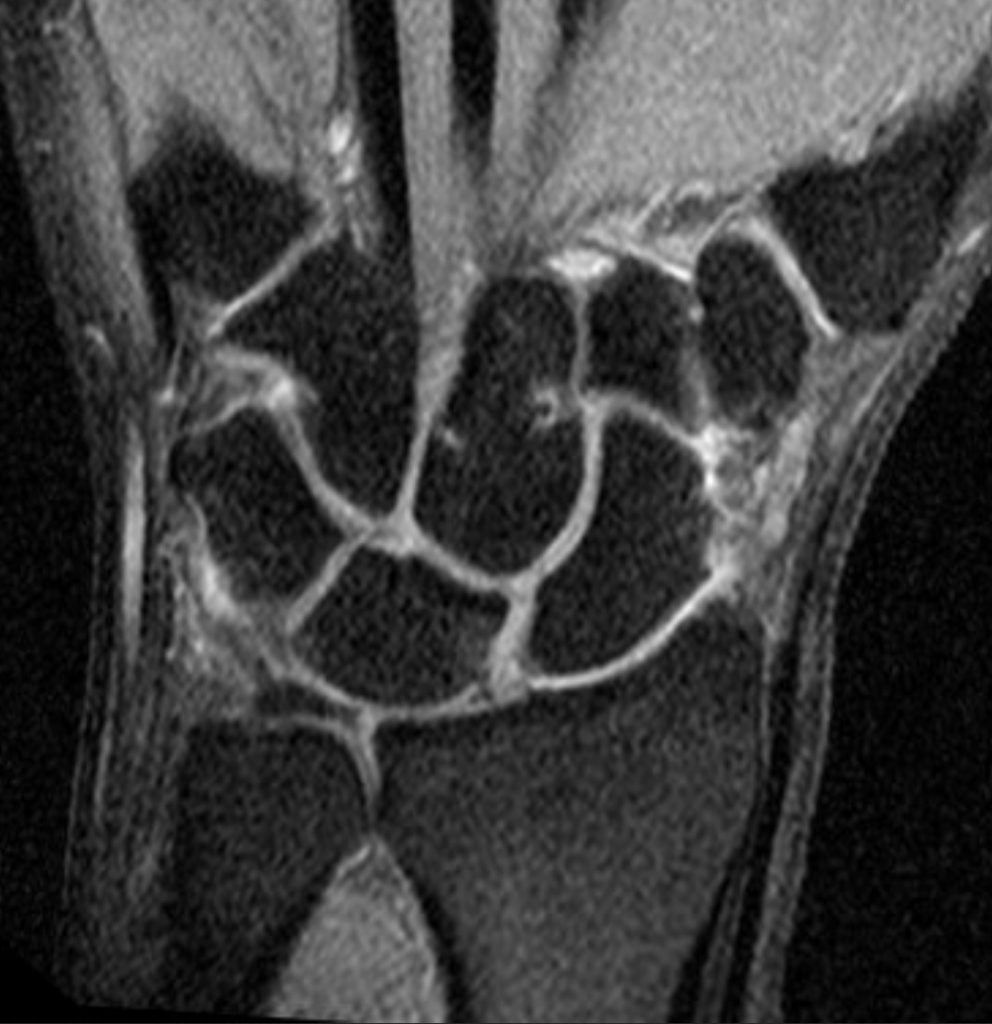

Clínicamente, el paciente refiere dolor en el dorso de la muñeca, especialmente al extenderla o al cargar peso. Puede observarse tumefacción, chasquidos o sensación de inestabilidad. A la exploración, es positiva la prueba de Watson (desplazamiento del escafoides con dolor y resalte). El diagnóstico se confirma mediante pruebas de imagen: la radiografía puede mostrar un aumento del espacio escafolunar (“signo de Terry Thomas”) (Figura 1), mientras que la resonancia magnética o la artro-RMN (Figura 2) pueden visualizar directamente la lesión del ligamento. En casos dudosos, la artroscopia de muñeca es el “gold standard” diagnóstico (Figura 3).